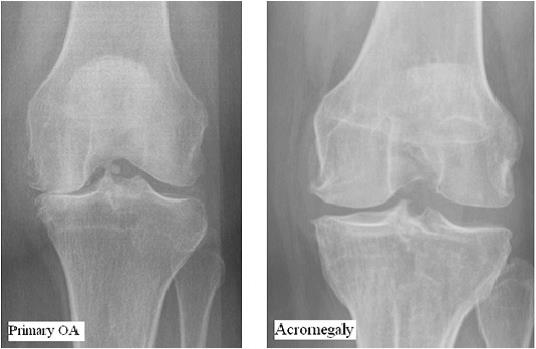

Стандартная рентгенография по-прежнему остается рекомендуемой визуализирующей методикой для оценки структурных изменений при остеоартрозе. Применяются различные инструменты и стандартизованные атласы для полуколичественного анализа признаков остеоартроза в каждом суставном компартменте [54]. Примеры таких методов — критерий OARSI (Международного общества по изу чению остеоартроза) [55], оценивающий сужение суставной щели (ССЩ) и отдельно — наличие остео фитов, а также критерий Келлгрена—Лоуренса [56] — суставной показатель, учитывающий и образование остеофитов, и сужение суставной щели. В отсутствие специфической системы классификации для акромегалической артропатии предлагается использование классификации OARSI из-за возможности раздельного учета наличия остеофитов и ССЩ как независимых диагностических критериев [57]. Однако важным ограничением этих неспецифических классификаций является отсутствие в них признака, с наибольшей вероятностью отражающего тяжесть акромегалической артропатии, — расширения суставной щели.

Таким образом, акромегалическая артропатия характеризуется тяжелым остеофитозом, но суставные щели скорее расширены, чем сужены, тогда как преобладающий признак при первичном остеоартрозе — ССЩ. Избыток СТГ предохраняет от потери хрящевой ткани, что проявляется стойкой гипертрофией хряща. Хотя некоторые УЗ-исследования демонстрируют частичную обратимость расширения суставной щели после терапии аналогами соматостатина [56], характерный рентгенологический фенотип акромегалической артропатии у большинства пациентов сохраняется и после достижения биохимического контроля заболевания [6, 57]. Вместе с тем у небольшой подгруппы пациентов наблюдались противоположные изменения (ССЩ) [58]. У этих пациентов суставные симптомы были особенно выраженными. Отмечена ассоциация ССЩ с продолжающимся избыточным воздействием СТГ/ИФР-1 и временем до проведения хирургического лечения.